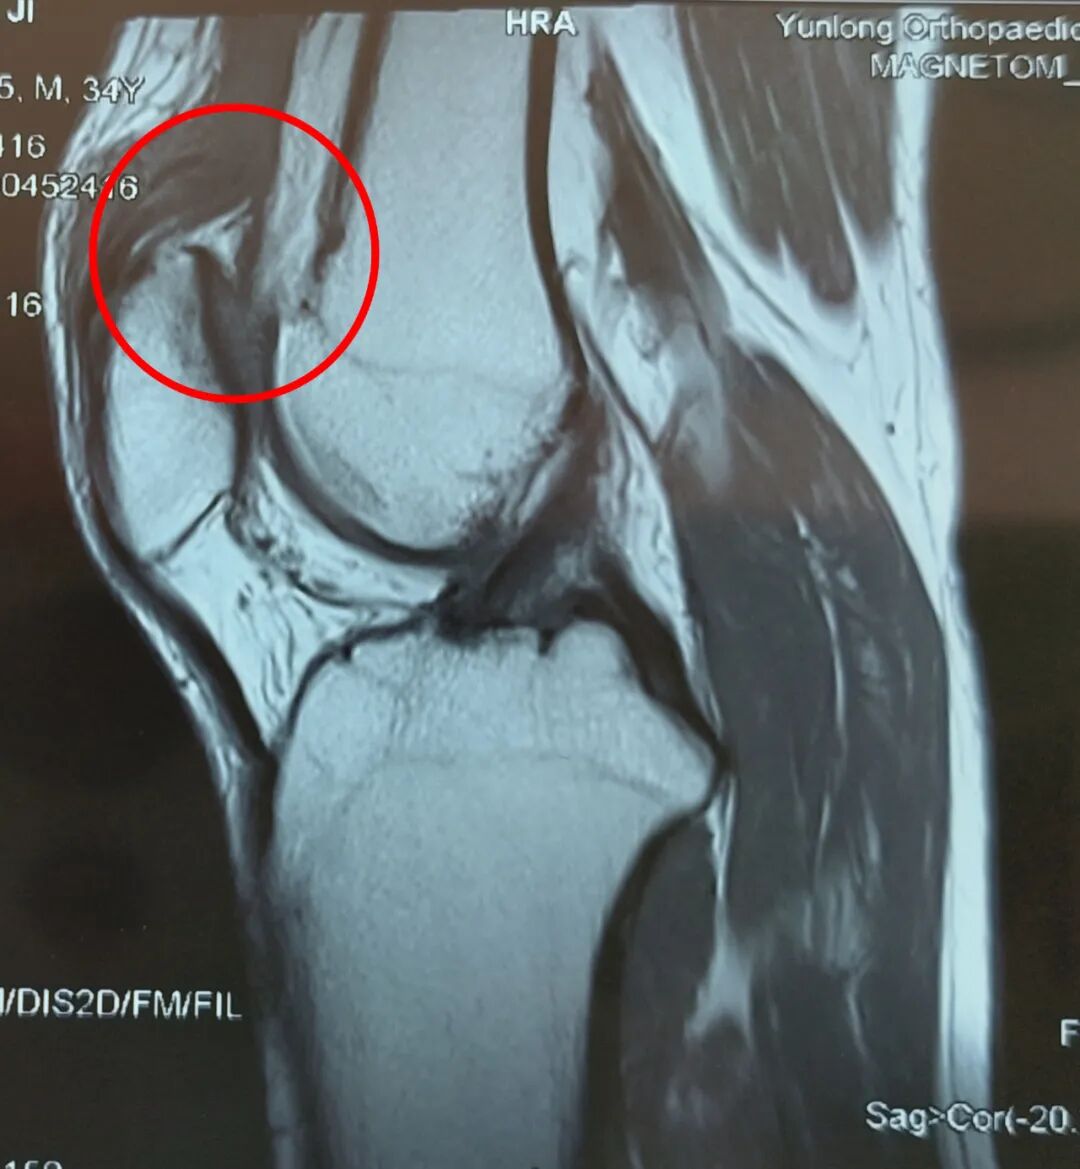

磁共振的检查结果显示,孙先生的股骨股四头肌断裂,也就是连接大腿和膝盖之间的肌腱断裂了。

患者肌腱断裂核磁影像